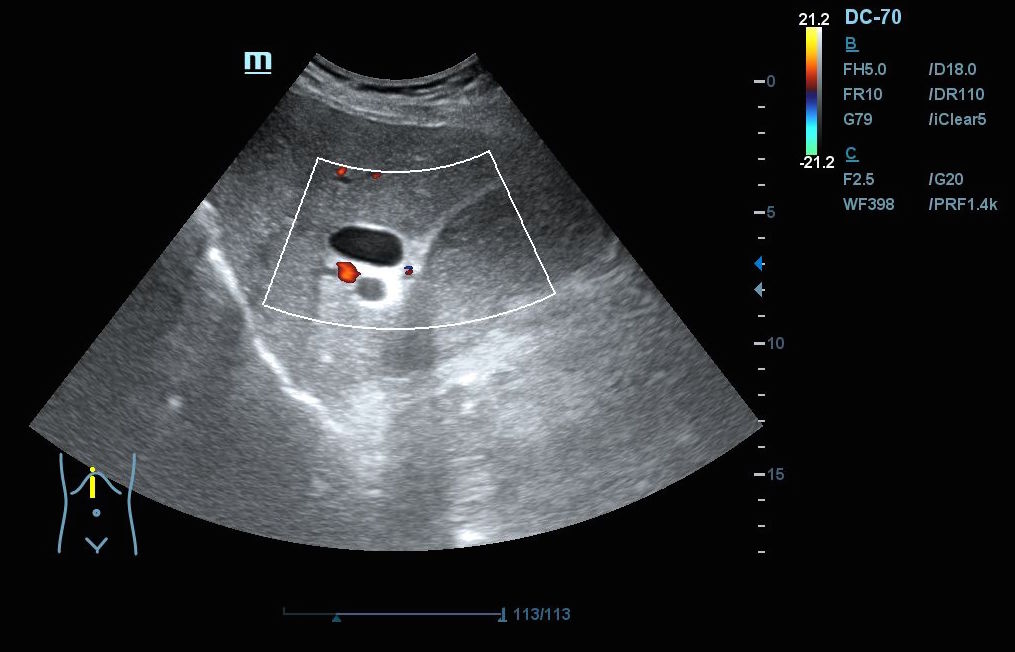

Hallazgos ecográficos: En el epigastrio se observa una imagen anecoica tubular, sin captación en Doppler, con un diámetro mayor a 2 cm, que sugiere una dilatación del colédoco (imagen 1). La vesícula biliar se encuentra completamente distendida y hepatizada, con una imagen en «doble cañón de escopeta» sugestiva de colestasis (imagen 2). En los cortes longitudinales se identifica una masa anterior a la aorta en el corte paramedial izquierdo, aparentemente localizada en el cuerpo del páncreas (imagen 3). En los cortes transversales se observa una masa que afecta tanto al cuerpo como a la cabeza del páncreas (imagen 4).